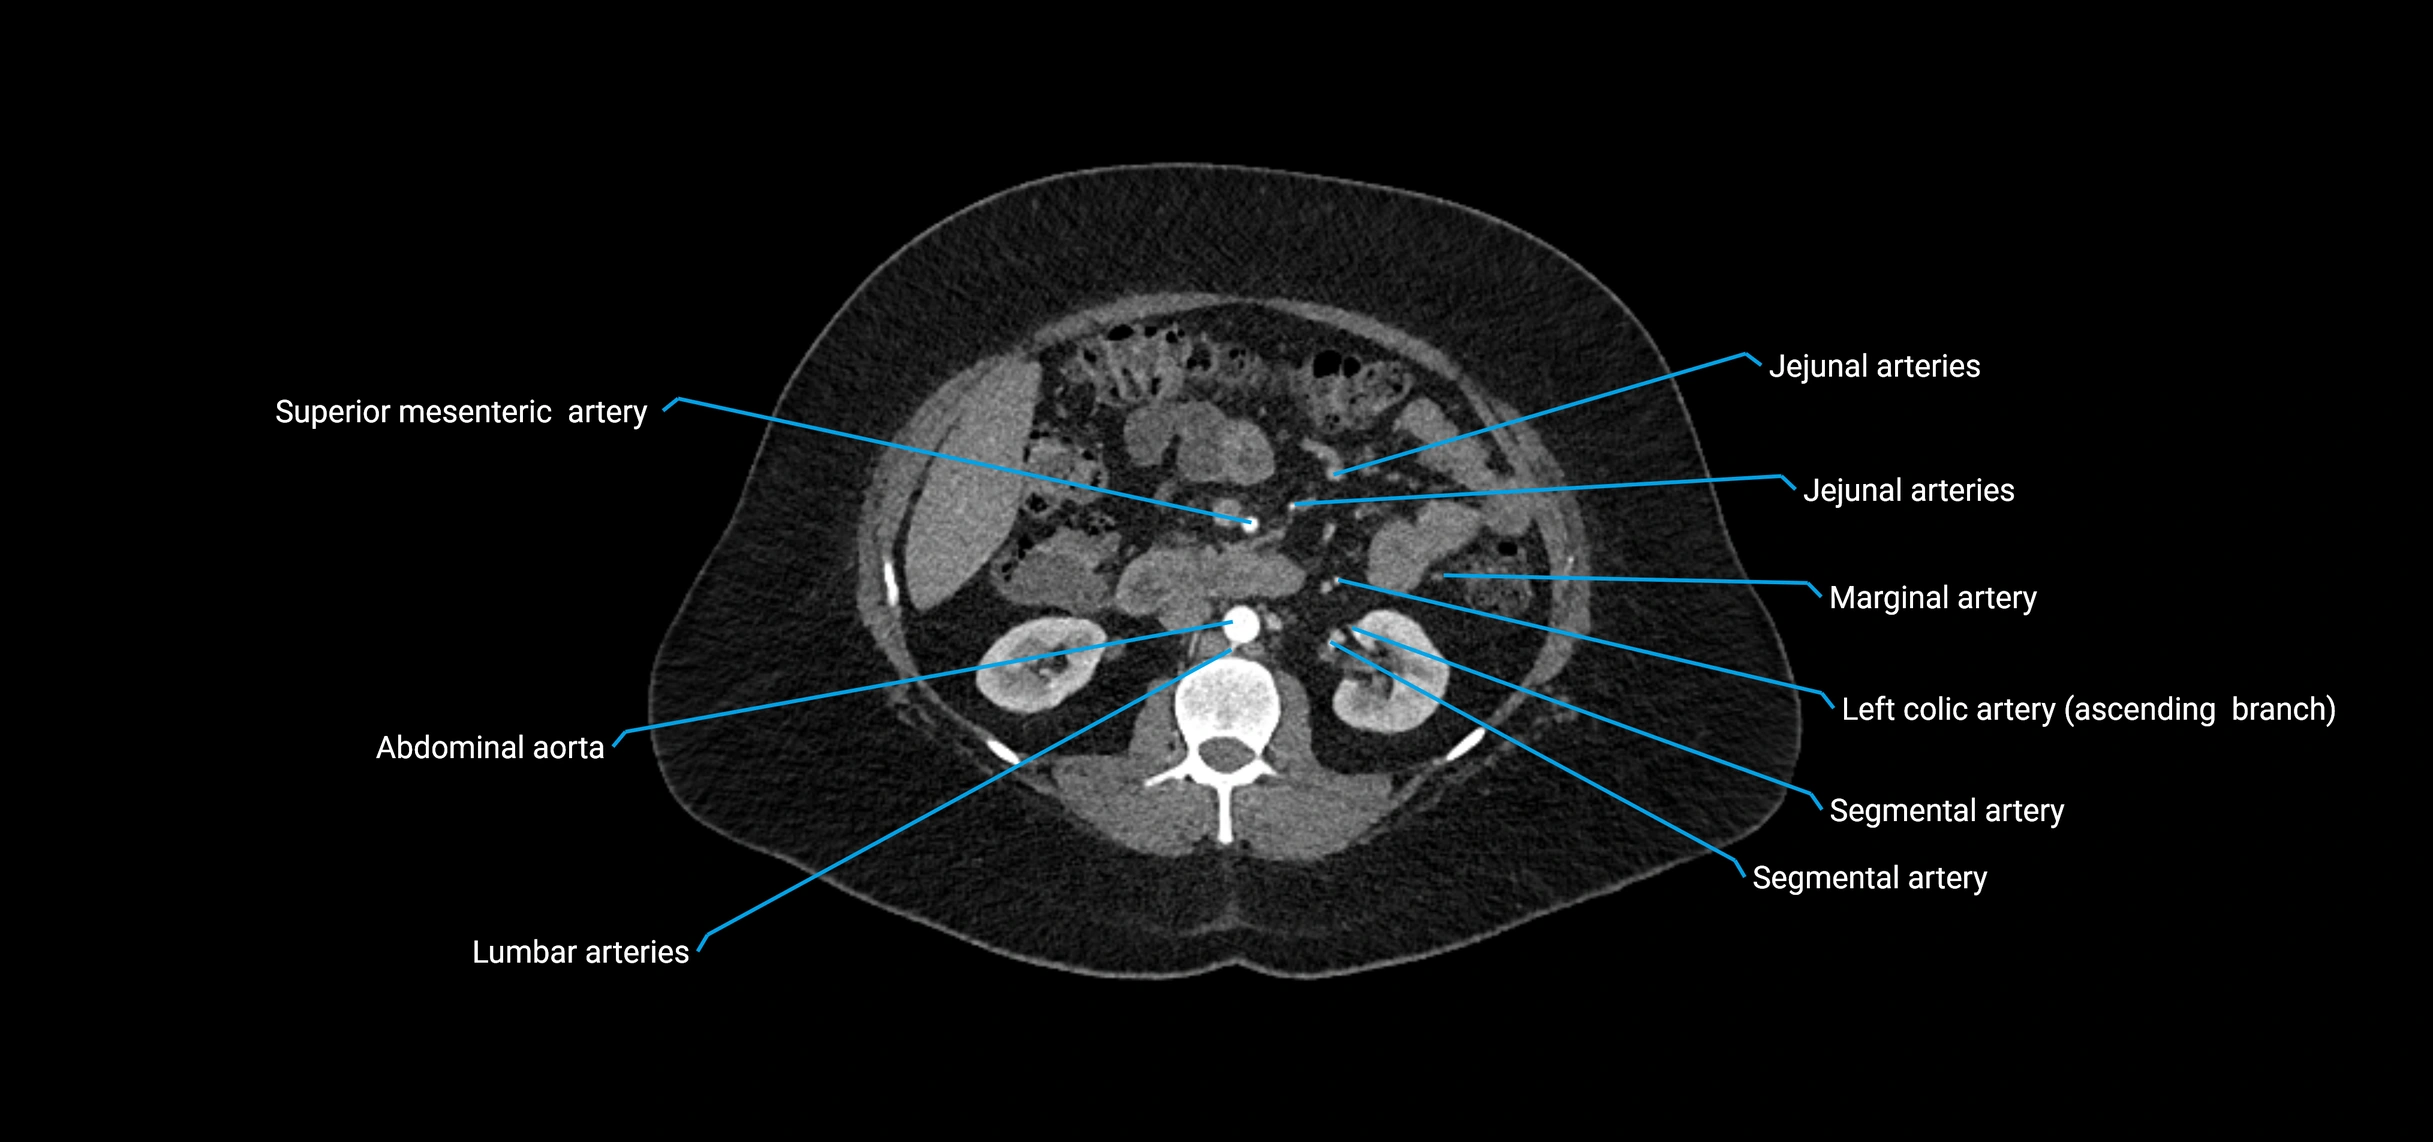

CT Appearance

Non-contrast CT:

• Appears as a tubular soft tissue structure anterior to vertebral bodies

• Calcified atherosclerotic plaques appear as hyperdense foci along the wall

• Useful for screening abdominal aortic aneurysm (AAA) size and mural calcification

Contrast-enhanced CT (CTA):

• Gold standard for abdominal aortic imaging

• Provides excellent detail of lumen, wall, aneurysm, thrombus, and branch vessels

• Multiplanar and 3D reconstructions help in aneurysm measurement, stent graft planning, and dissection evaluation

• Detects acute rupture, traumatic injury, or occlusion with high sensitivity

CT images

image